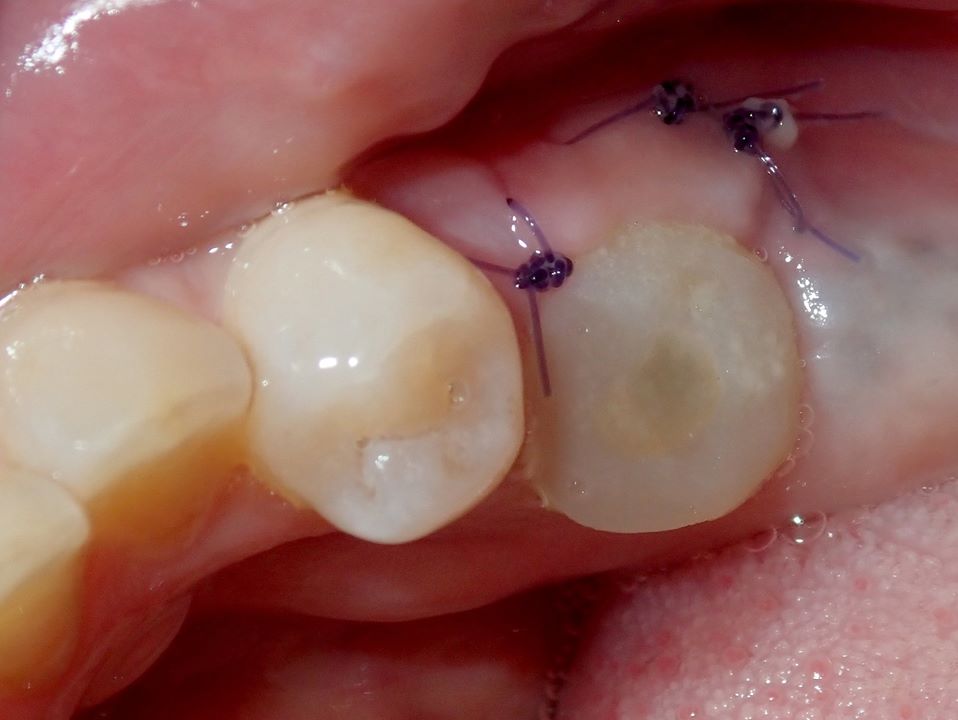

A 4.8 mm x 10 mm implant (Straumann® Bone Level Tapered [BLT], Straumann) had been placed at the mandibular first molar site and was ready for restoration. A custom healing abutment was fabricated and inserted at the time of surgical implant placement and soft tissue was sutured around the abutment using 4/0 Glycolon sutures (Osteogenics Biomedical, osteogenics.com) (Figure 13). A periapical x-ray was taken at the time of placement of the custom healing abutment to confirm full seating (Figure 14).

Fig 13. A custom healing abutment was created to replicate the emergence profile for a mandibular molar, which is square in cross-section.

Figure 13